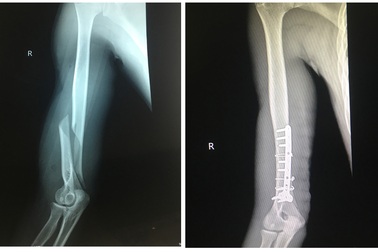

Nam thanh niên bất ngờ gãy gập xương khi vật tay với bạnĐang thử sức cùng bạn bằng trò vật tay, bất ngờ sau tiếng “cụp” cánh tay phải của nam thanh niên gãy gập. Xương gãy xoắn phức tạp khiến nạn nhân đối mặt với nguy cơ liệt thần kinh quay.

Chơi vật tay với bạn, thanh niên 19 tuổi bị gãy xương cánh taySau khi đọ sức cùng bạn thông qua trò vật tay, nam thanh nhiên ở Quảng Yên, Quảng Ninh phải vào viện cấp cứu. Xương cánh tay bị gãy vặn xoắn một đoạn khoảng 8cm.